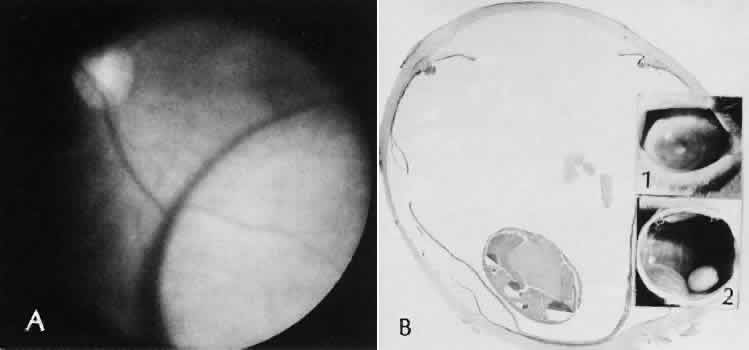

Fig. 28. A case of lens capsular rupture during intracapsular cataract extraction. On postoperative day 1 (inset 1), there was considerable retention of lens capsular material nearly obscuring the anterior chamber. By postoperative day 14 (inset 2), considerable clearing of debris has occurred. At 2 months following surgery (inset 3), the anterior chamber was nearly clear. The clearing of the debris was through the action of macrophages ingesting the cortical debris and exiting the eye through the trabecular apparatus. Macrophages filled with lens cortical material from a different case are seen in the main figure. (Periodic acid-Schiff stain; × 700.) (Yanoff M, Scheie HG: Cytology of human lens aspirate. Its relationship to phacolytic glaucoma and phacoanaphylactic endophthalmitis. Arch Ophthalmol 80:166–170, 1968.)

Fig. 29. Iris and lens capsule have been incarcerated in this limbal wound performed because of cataract surgery. The displaced anatomy completely altered anterior chamber physiology and lead to loss of the eye from intractable glaucoma. Because the material of Descemet's membrane cannot be remodeled by the proteolytic enzymes of the wound healing process, the wound with incarcerated materials such as this will remain unhealed and weak, and will be a possible route for microbial infection. (Periodic acid-Schiff stain; × 16.)